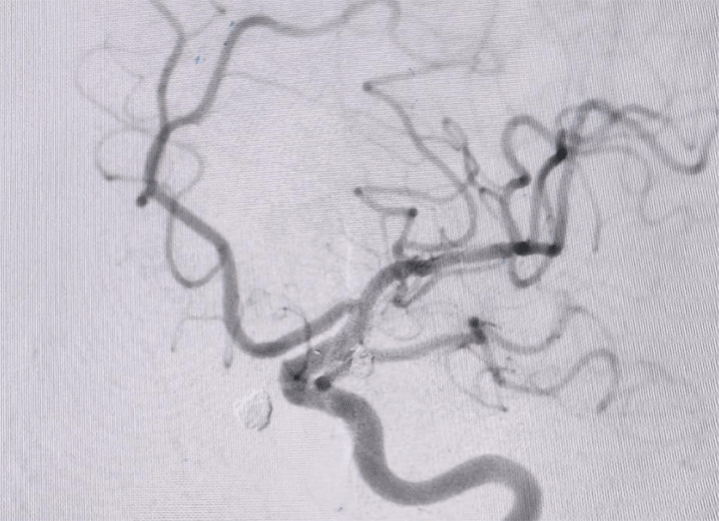

手术过程顺利,医生们凭借丰富的经验和精湛的技术,成功完成了左侧动脉瘤的处理,手术栓塞效果令人满意。由于是未破裂动脉瘤,患者恢复速度较快,术后仅3天就达到出院标准。

据吴全主任介绍,颅内动脉瘤破裂出血是一种极其凶险的疾病,死亡率和致残率都很高。在面对复杂的血管条件和双侧动脉瘤的情况时,分阶段处理是一种科学合理的治疗策略。第一次优先处理破裂的责任动脉瘤,保障患者生命安全;第二次在患者身体恢复良好的情况下处理未破裂动脉瘤,消除潜在隐患。这种治疗方案既降低了手术风险,又提高了患者的治愈率和生活质量。